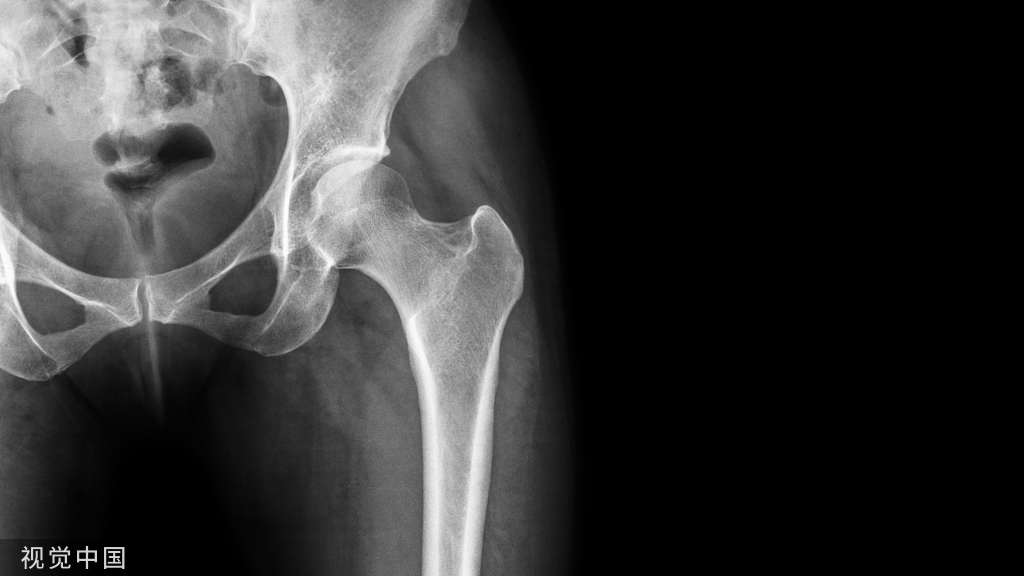

2.股骨远端截骨

膝关节内翻畸形常源于胫骨畸形,因此股骨远端截骨常做标准的5°~7°外翻截骨。在股骨远端放置截骨导向板,在膝内翻时,内侧紧贴在硬化的骨关节面上,而外侧通常与完整的软骨面贴附。